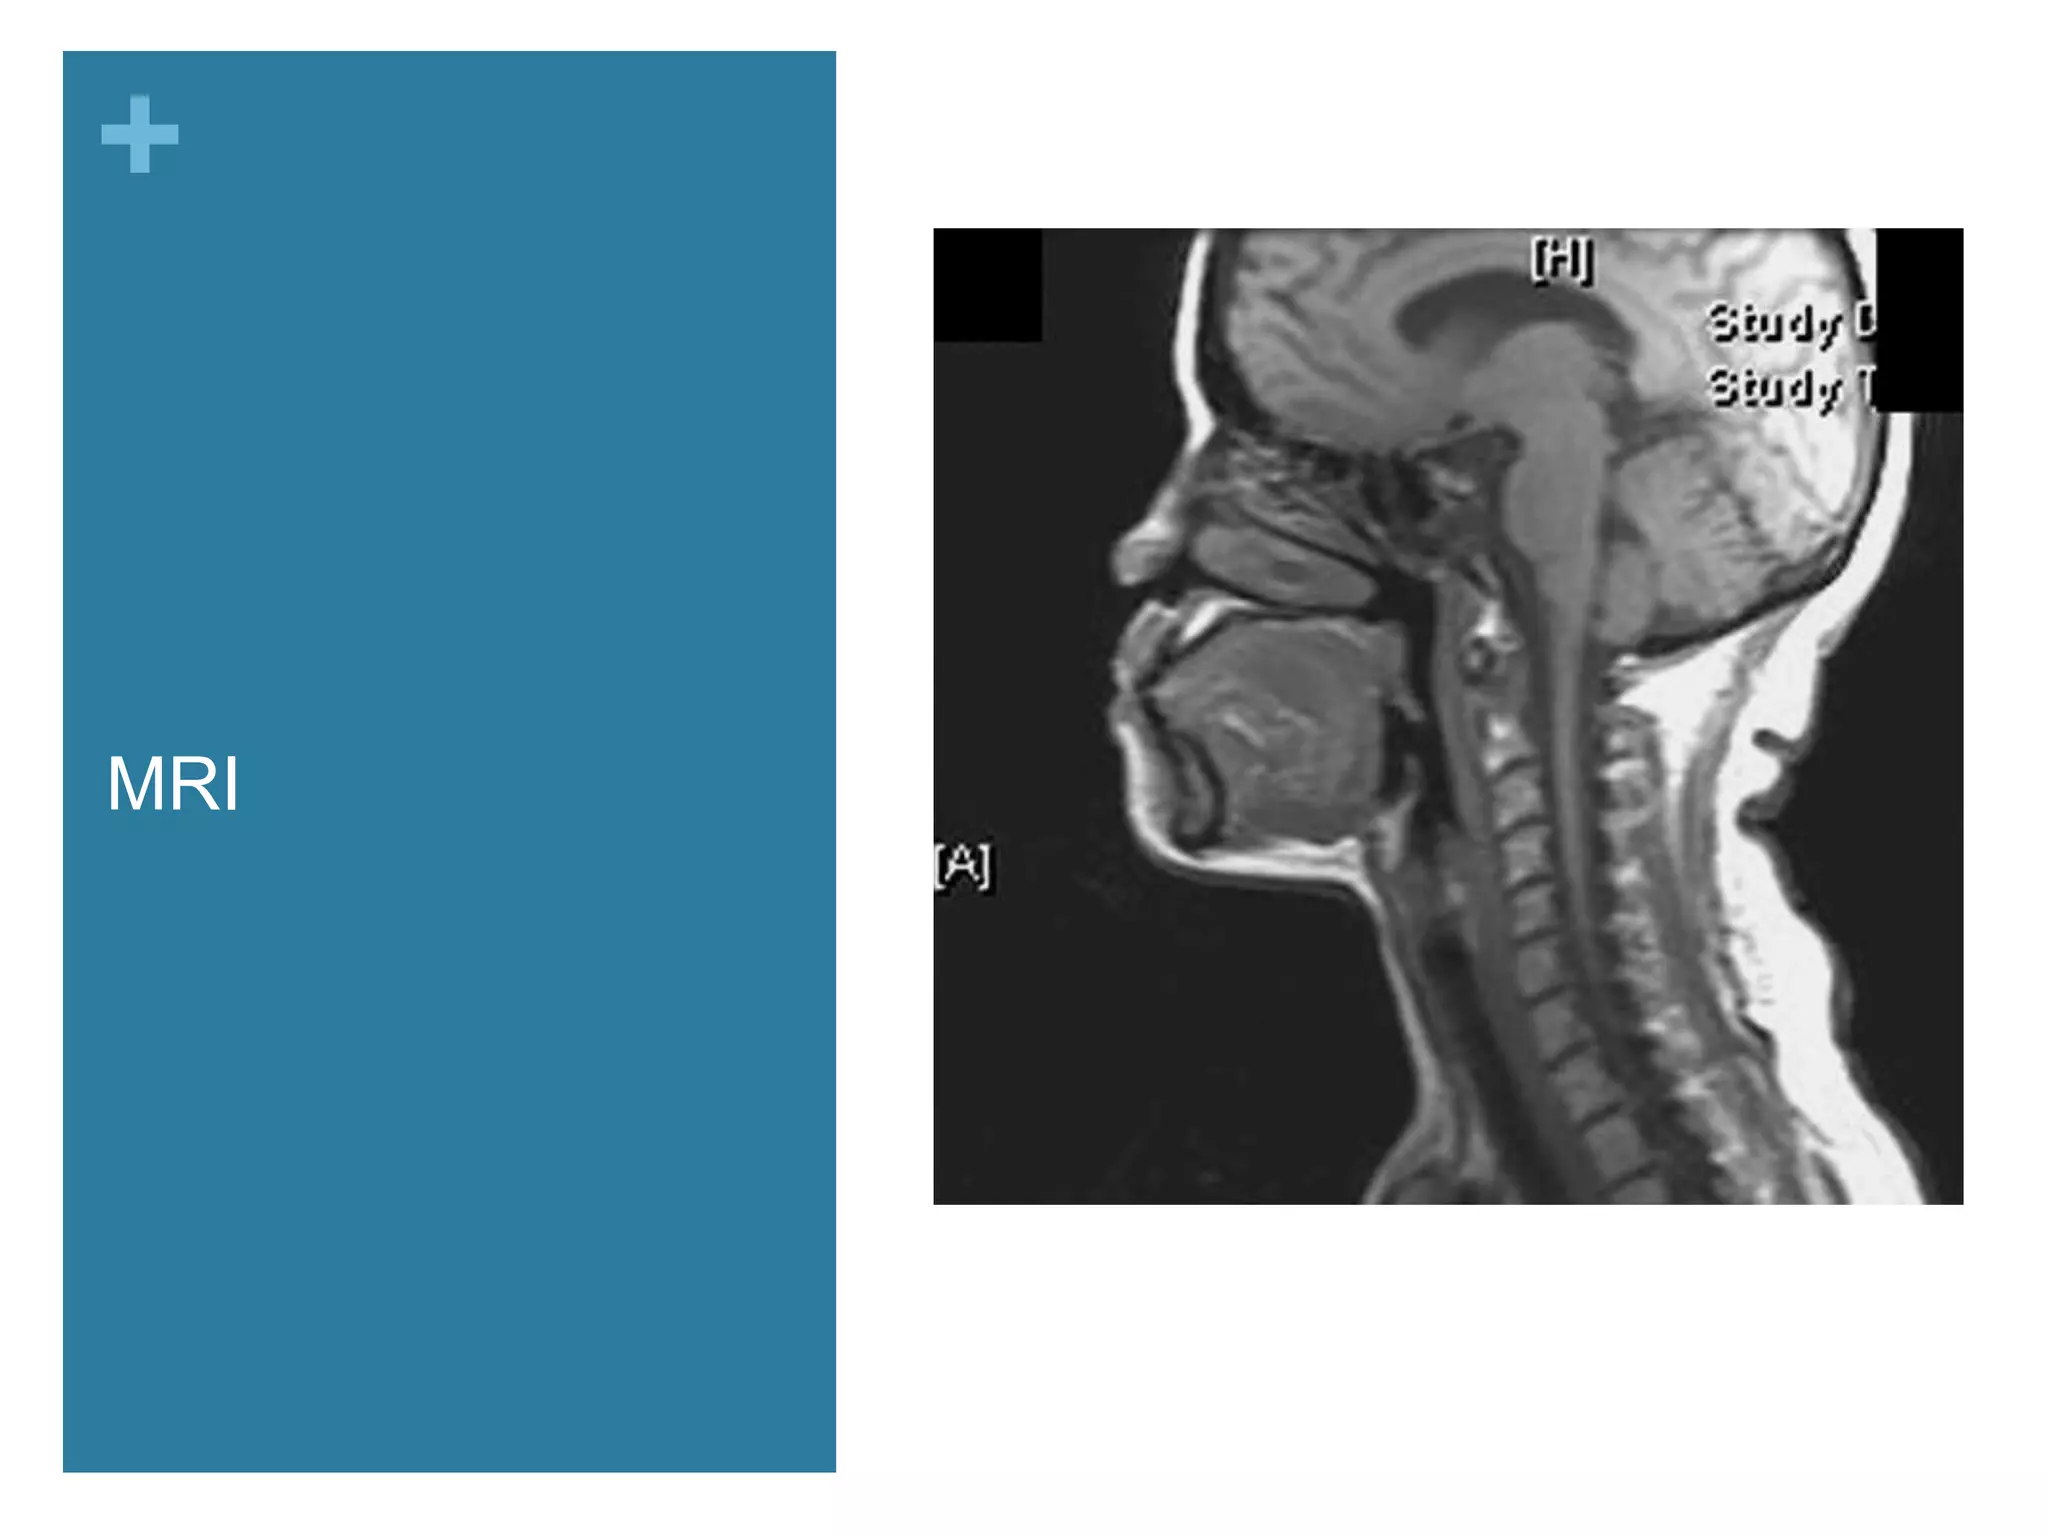

MRI